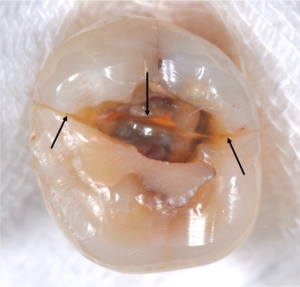

すると吸収部にはただ単に歯が溶けているのではなく、肉芽という歯茎の一部が入り込んでしまっているので、穴を開けた瞬間に血が噴き出してきて、血まみれで中を見るのが困難な状態でした。

そこで肉芽を様々な器具や技で除去をし、出血を止め薬剤で消毒しました。